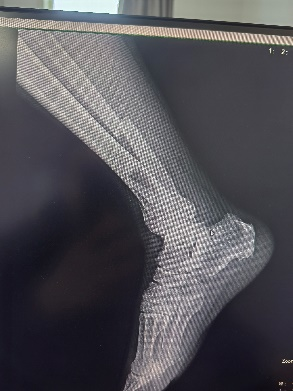

患者55歲男性,高處墜落致右側小腿腫痛伴活動受限,影像檢查顯示脛腓骨下端骨折,行機器人輔助下復位及外固定架固定。